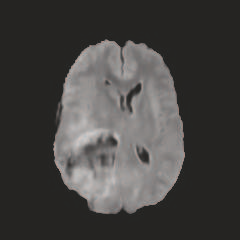

Multi-modal medical image completion has been extensively applied to alleviate the missing modality issue in a wealth of multi-modal diagnostic tasks. However, for most existing synthesis methods, their inferences of missing modalities can collapse into a deterministic mapping from the available ones, ignoring the uncertainties inherent in the cross-modal relationships. Here, we propose the Unified Multi-Modal Conditional Score-based Generative Model (UMM-CSGM) to take advantage of Score-based Generative Model (SGM) in modeling and stochastically sampling a target probability distribution, and further extend SGM to cross-modal conditional synthesis for various missing-modality configurations in a unified framework. Specifically, UMM-CSGM employs a novel multi-in multi-out Conditional Score Network (mm-CSN) to learn a comprehensive set of cross-modal conditional distributions via conditional diffusion and reverse generation in the complete modality space. In this way, the generation process can be accurately conditioned by all available information, and can fit all possible configurations of missing modalities in a single network. Experiments on BraTS19 dataset show that the UMM-CSGM can more reliably synthesize the heterogeneous enhancement and irregular area in tumor-induced lesions for any missing modalities.